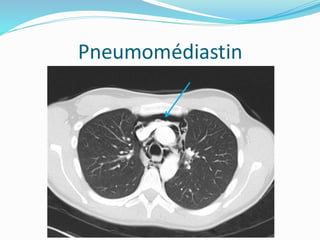

Pneumomédiastin

3e question : pneumomédiastin ?

 Signe du diaphragme continu.

 Hyperclarté péricardiaque.

 Collections aériques linéaires, au niveau des parties

molles du cou et de la paroi thoracique.

 Présence d`air autour de l`artère pulmonaire et de ses

branches.

 Collection aérique autour des troncs supra-aortiques.